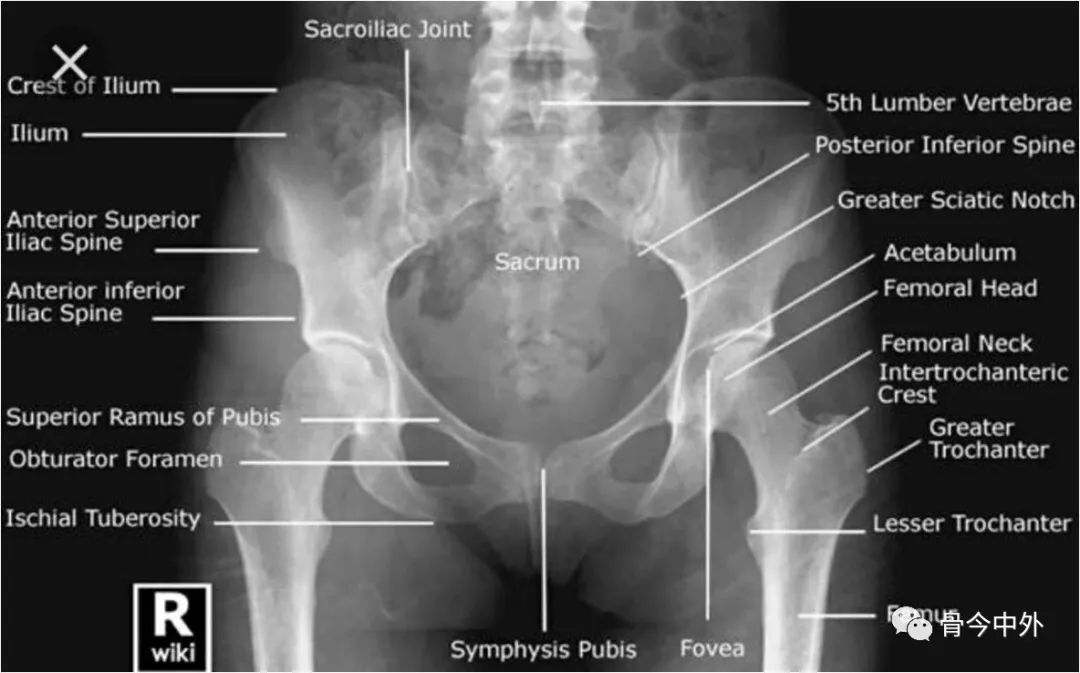

标准的骨盆X线片(前后位)

判断标准Criteria:对称

髋关节和骨盆影像学测量的应用:

股骨的评估

髋臼的评估

骨盆连续性的评估